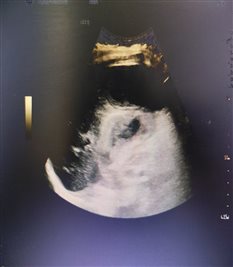

患者女性,72岁,腹痛十余天来诊,胆囊炎病史。超声发现胆囊底部穿孔并肝脓肿形成,范围约8.4×6.5×4.6cm,外科会诊后建议超声引导下穿刺引流脓肿,15日上午由特检科郭连香医师顺利完成肝脓肿置管,引流出脓液约100 ml。患者一般状况良好,安返病房。

穿刺置管引流后,脓腔明显变小。